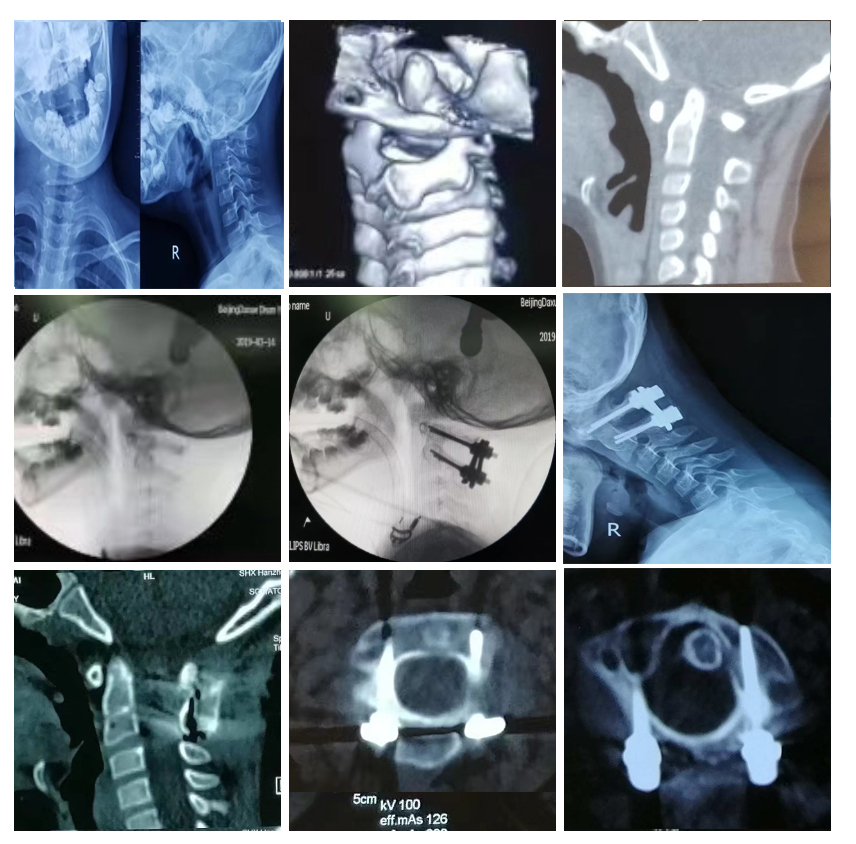

典型病例二:经典“后路枕颈固定植骨融合术”

60岁女性,寰椎枕化,寰枢关节脱位,颅底凹陷。术前斜坡枢椎角128°(图3),寰枢侧块关节面向前下倾斜(图4)。

麻醉后装上颅骨牵引弓,摆成俯卧位,用1/5体重做牵引。透视见寰椎被提起来了(图5)。利用钉板装置做压板复位、固定,髂后开窗,掏取松质骨,剪成颗粒状,置于枕骨与枢椎后弓间。1年后的复查影像见植骨充分融合了,斜坡枢椎角150°,寰枢侧块关节向前张嘴了。

典型病例五:小儿“寰枢关节旋转固定性脱位”的治疗

9岁男孩,耳廓手术后出现斜颈8个月,诊断为“寰枢关节旋转固定性脱位”。

俯卧位施术,颅骨牵引复位,做后路寰枢侧块钉板固定,椎弓根钉直径3.0毫米。术后未用外固定。植骨融合成功。